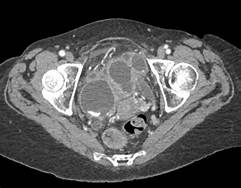

脓肿位置可能不一样,膈下脓肿,腹腔脓肿,肠间脓肿或者盆腔脓肿的诊断可以通过各种影像学特征来完成。虽然脓腔的CT和超声特征已经阐述清楚,但其他腹腔内液体的聚集,例如血肿,胆汁瘤,囊状淋巴管瘤和囊肿等都应该区分开。而且,既然没有好办法事先确定积液内是否存在感染,不论何时只要有临床可疑时都应改进行穿刺引流。

诊断腹部脓肿最有效并且最常用的两种方法是CT和超声。超声具有便捷,迅速,没有放射,便宜等优点。诊断的准确率和CT相同。可以明确脓肿的大小、部位、深浅度,也可以在B超引导下穿刺进行诊断或引流。但是对于肥胖,肠梗阻,广泛性皮肤外伤/烧伤的病人就不能进行该检查。大多数病人,超声作为首选检查。脓腔典型的超声表现为无回声积液,其内带有一些回声性碎片。但是,根据内容物的不同,一些脓肿可能表现为混合回声或者高回声的病变。根据超声的特点进行脓肿病因的诊断还存在一些困难。

CT不依赖操作者的技术和身体条件能够提供更加标准的信息。当脓腔完全浊化时,诊断的准确率几乎在95%以上。另外,CT还能为经皮穿刺引流提供精确的引导(甚至可以使用透视CT进行实时引导)。当许多人认为当可疑存在腹部脓肿时超声为首选影像学手段时,也有很多人认为CT是性价比最高的影像学检查方法,因为它很高的精确度和特异性。在腹部脓腔探测方面,肠袢间不充分的肠壁模糊是基本要素。